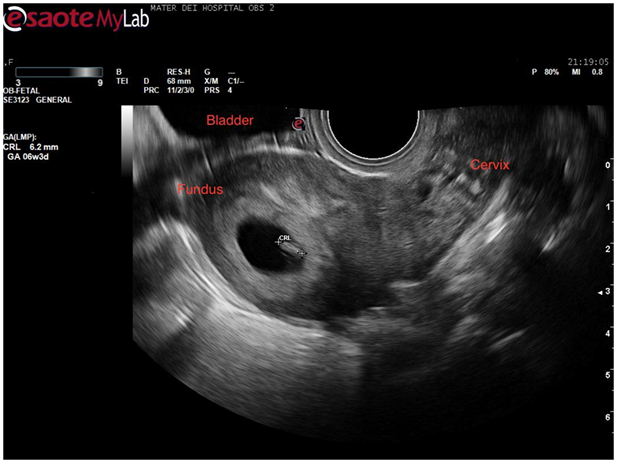

At this stage a decision was made to proceed to transvaginal scan in the hope of mapping the coils’ location better. Once again verbal consent was obtained and after covering the patient with a modesty sheet the high-frequency endovaginal probe was gently introduced after covering with gel and a probe cover. The images obtained confirmed the findings of the abdominal scan (Figure 5). By rotating the probe anticlockwise the uterus could be visualised in its transverse diameter. This view is a good one for demonstrating separation of the endometrial stripe into 2 as the uterus is scanned from a caudal to a cephalic direction. On reaching the fundus 2 definite horns are usually visualized (Figure 6). In this case, a gestation sac was distending the left horn as demonstrated in Figure 7. The rest of the examination was normal with both adnexae visualised and appearing normal.

Figure 5 Sagittal view of uterus demonstrating right horn of endometrial cavity with echogenic coil within.

Figure 6 Sagittal view of uterus demonstrating intrauterine sac with fetal pole equivalent to 6weeks and 3 days gestation.